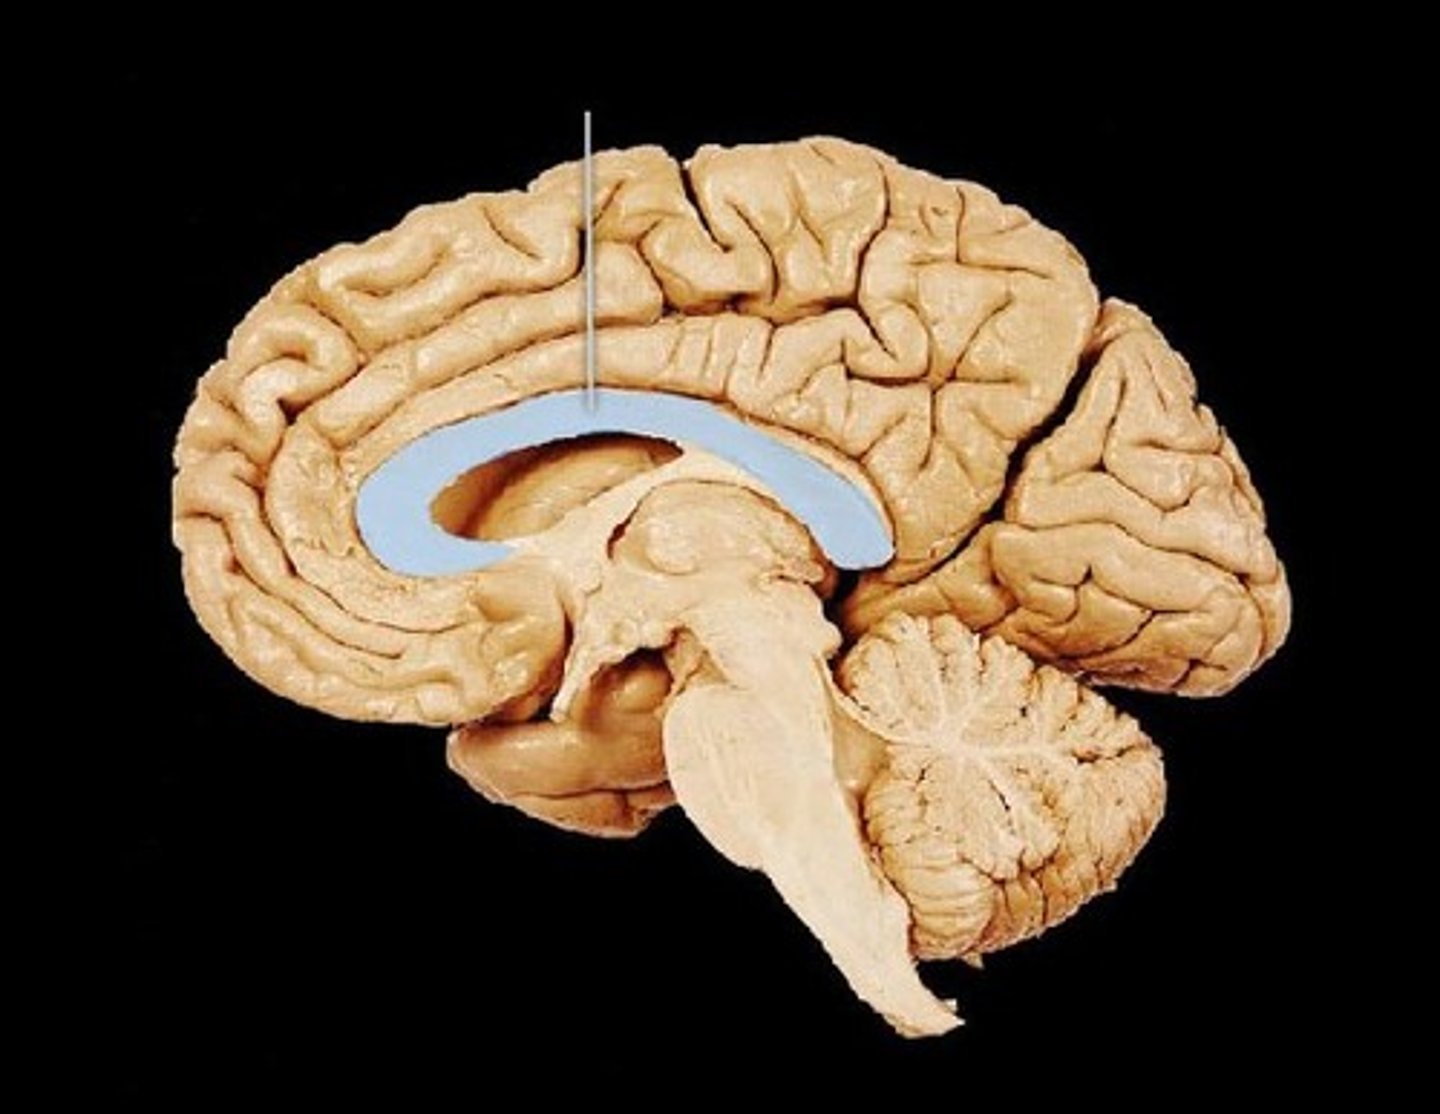

Corpus Callosum

Fibers connecting both halves of the brain, c shaped structure

Fornix

fiber tract linking limbic system regions

Diencephalon

made up of epithalamus, thalamus and hypothalamus

Thalamus

bilateral egg shaped nuclei connected by interthalamic adhesion and forming superior wall of 3rd ventricle. relay station for info coming from cortex.

Hypothalamus

forms floor of 3rd ventricle , cap over brain dtem and 3rd ventricle. Visceral control center, 3 fs

Septum Pellucidum

separates lateral ventricles

third ventricle

formed from diencephalon. Superior to hypothalamus; lies between right/left halves of thalamus